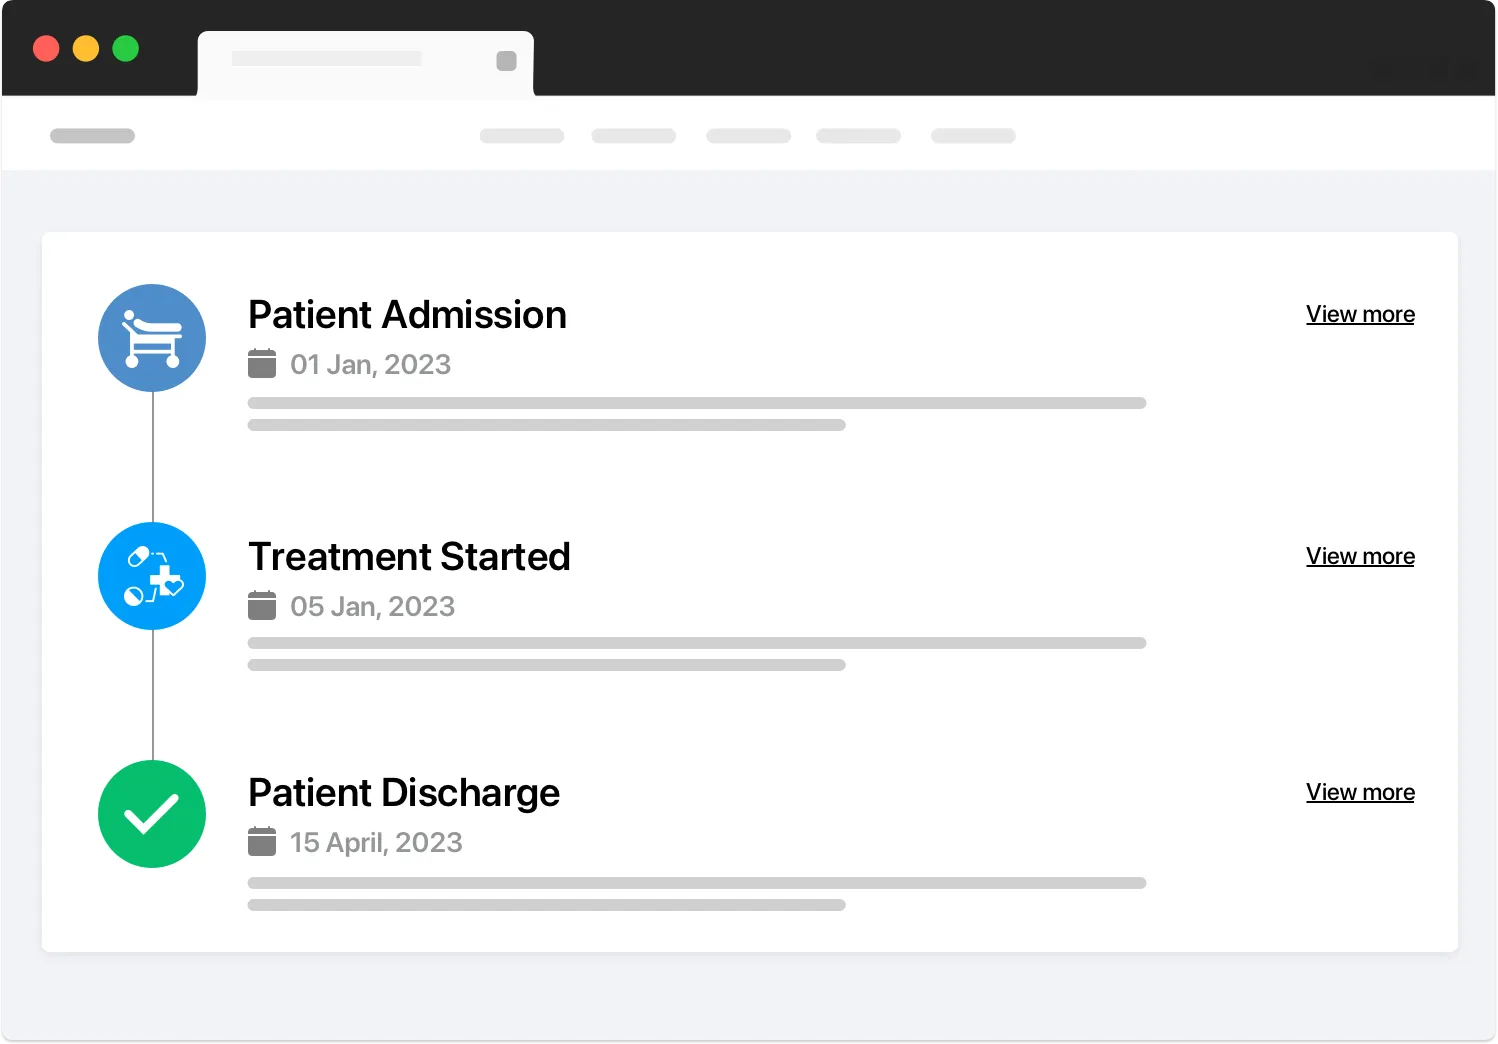

Health History: Maintain a comprehensive history of patient health records.

Treatment Plans: Customizable and manageable treatment plans.